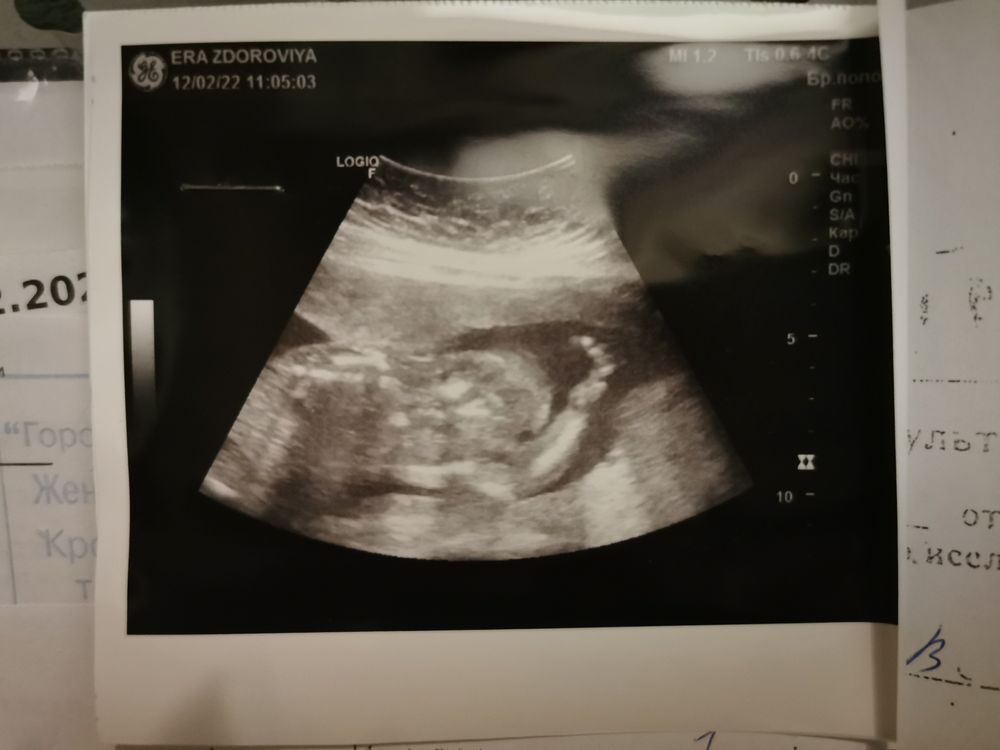

Сходу сказали, что моловолье и гипертонус в этом месте, странно, что мазки без инфекций (но я переболел ковидом недавно). А ещё гипотрофия плода (на этом месте стало понятно, что тётка не в адеквате, тк еще полторы недели назад размеры и все все были больше срока, к слову это 19 недель, сейчас 20 недель). Тетка стала рассказывать про знакомую, которая решилась родить гипотрофированного плода и оьрекла ребёнка на вечные муки, ибо вообще-то нужно прерывать. . И ещё кучу всего нарассказала 😅

В заключении написала вес плода 500 гр (20 недель, гипотрофия), какие-то двузначнве цифры в размерах по мм, я совсем не поняла. И просто маловодье.

П. С. И фотка узи какая-то стремная получилась, я не на экране ничего не видела и тут хорошо муж был со мной рядом 😅 потом спрашивала, что на экране на самом деле было